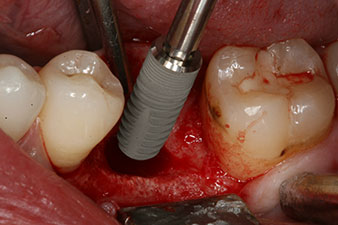

Имплантът е поставен както е планирано след цялостно отстраняване на гранулационната тъкан (blueSky, bredent).

Въртящият момент, използван за машинно-задвижвано поставяне, е 43 Ncm. Освен това, след завинтване на измервателния щифт (SmartPeg), специално пригоден за импланта, стойността на ISQ се измерва със сондата на W&H Osstell ISQ модула.

Този модул е допълнителна екстра към Implantmed на W&H и е закачен към имплантологичния мотор (виж фиг. 11). Липсата на ISQ стойност непосредствено след поставянето е 64 оровестибуларно и 68 мезиодистално (максимална стойност = 100).

Тези стойности могат да показват отворено лечение или дори имедиатно възстановяване. Поради недостатъчния обем на кресталната кост при импланта, областта е подсилена с костните частици, събрани по време на препарацията на имплантното ложе и зашити, за да се изолира слюнката.